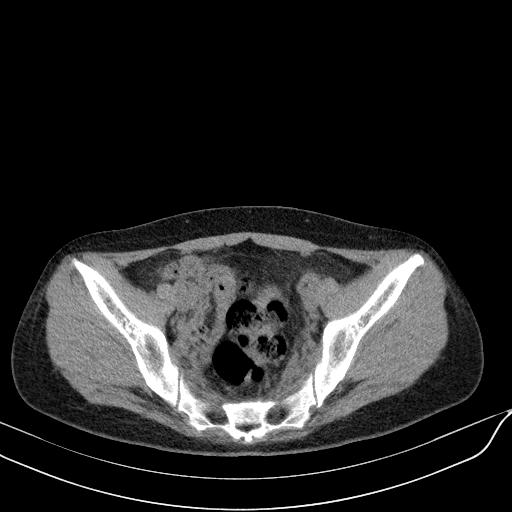

标题: CT23965:无外伤史,下腹痛 [打印本页]

标题: CT23965:无外伤史,下腹痛

肠道未准备,继续往下扫,乙状结肠占位不排除。建议钡灌或结肠镜检查。

乙状结肠占位不排除

回肠间质瘤?

肠道肿瘤,建议行钡剂灌肠检查。